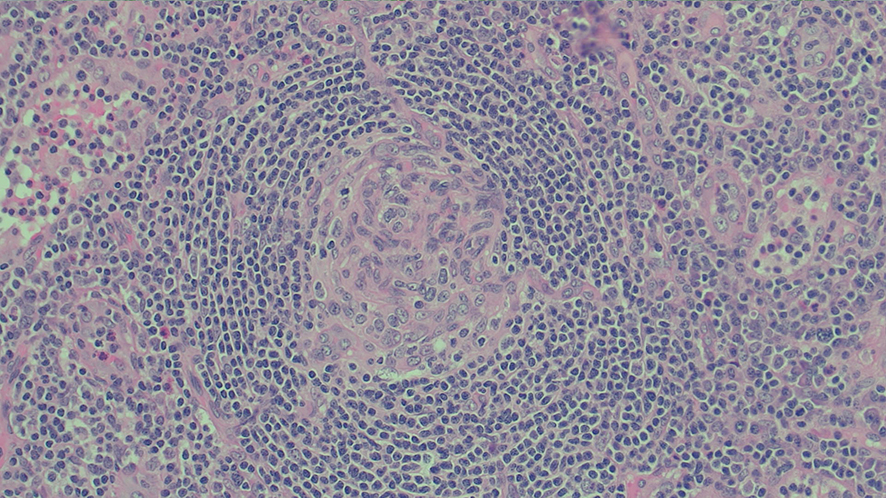

A positron emission tomography scan showed innumerable mildly to moderately fludeoxyglucose (FDG)‐avid enlarged and non‐enlarged lymph nodes above and below the diaphragm, and increased splenic and bone marrow activity (Box 3). Biopsy samples were taken from the most FDG‐avid axillary and mediastinal lymph nodes, but were non‐diagnostic. The results from one biopsy showed non‐caseating granulomas; however, results from the second biopsy did not. An excisional lymph node biopsy was subsequently taken, with the results meeting histopathologic criteria for Castleman disease (Box 4). These criteria included depleted germinal centres, concentric rimming of small B lymphocytes in a “onion skin” appearance, and vascularity with vessels extending into the germinal centre.1